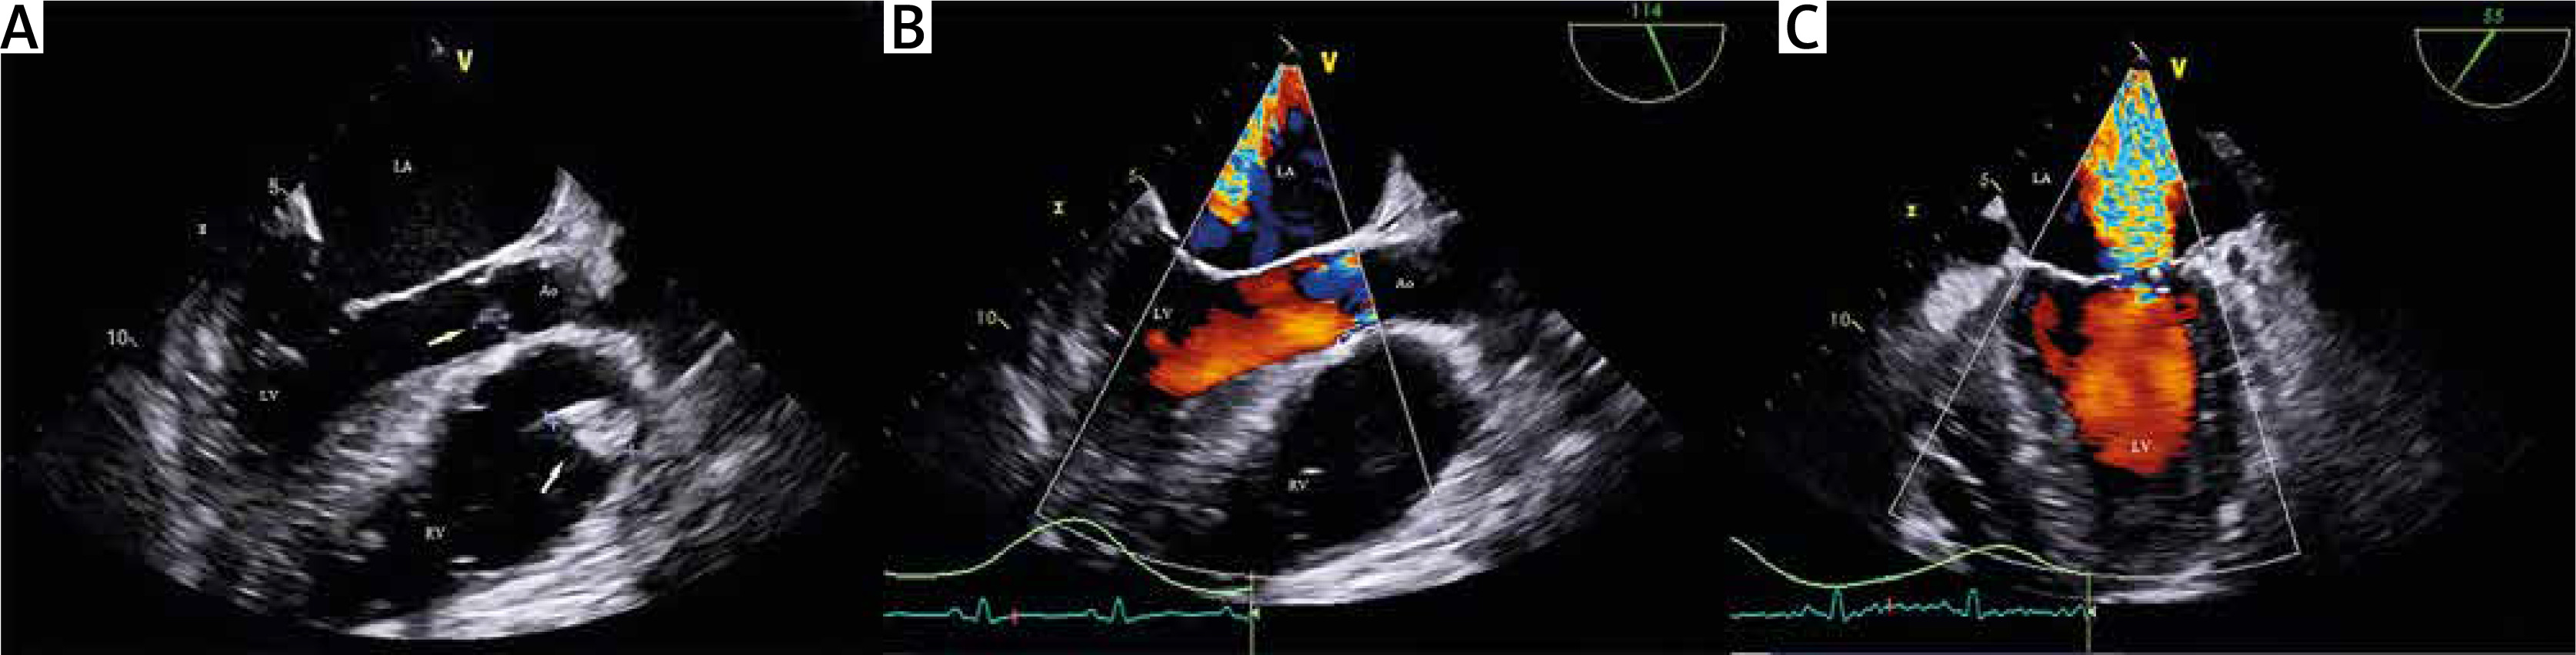

Figure 1

Transesophageal echocardiography examination: A – TEE revealed small vegetation on the aortic valve (yellow arrow) and more extensive vegetation on the pulmonary valve with protrusion into the RV. B – TEE colour Doppler examination revealed severe aortic valve regurgitation. C – TEE colour Doppler examination revealed severe mitral valve regurgitation

LA – left atrium, LV – left ventricle, RV – right ventricle, Ao – aorta.